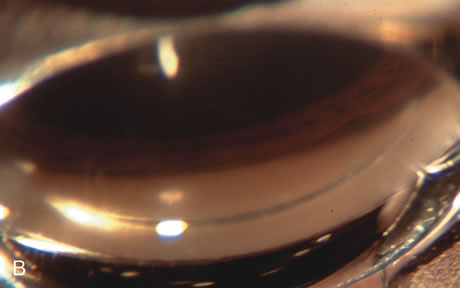

CATARACT EXTRACTION ALONE REDUCES IOP IN MOST EYES WITH ANGLE-CLOSURE GLAUCOMA Uncomplicated cataract extraction substantially reduces IOP, along with the number of postoperative glaucoma medications in eyes with angle-closure glaucoma.146,147 When preoperative gonioscopy reveals PAS, along with adjacent areas of appositional closure, lens extraction alone in select cases may be a reasonable alternative to filtration surgery.148,149 Phacomorphic angle-closure disease due to enlargement of the lens with progressive angle crowding is eliminated following lens extraction. The width and depth of the anterior chamber angle in eyes with angle-closure glaucoma increases significantly after cataract extraction with IOL implantation and becomes similar to open-angle glaucoma and normal eyes.150,151 (Fig. 5). Combining phacoemulsification, IOL implantation, and limited goniosynechialysis is effective in the treatment of cataract and chronic angle-closure glaucoma.152 Phacoemulsification with implantation of a foldable IOL is more effective in reducing IOP and improving visual acuity than surgical peripheral iridectomy in eyes with acute angle-closure glaucoma.153